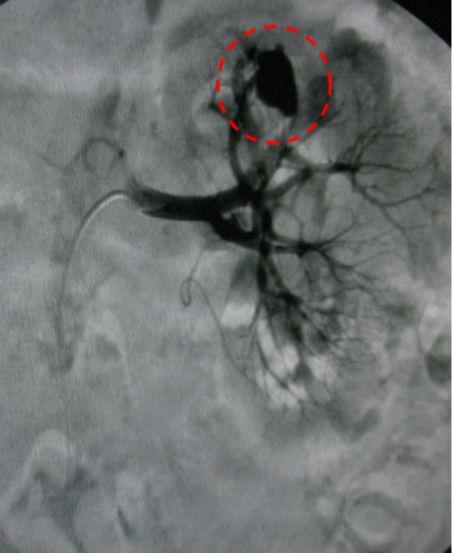

左肾取石术后血尿,造影发现左肾动脉分支出血。

治疗前

介入栓塞后出血停止,血尿消失。

治疗后